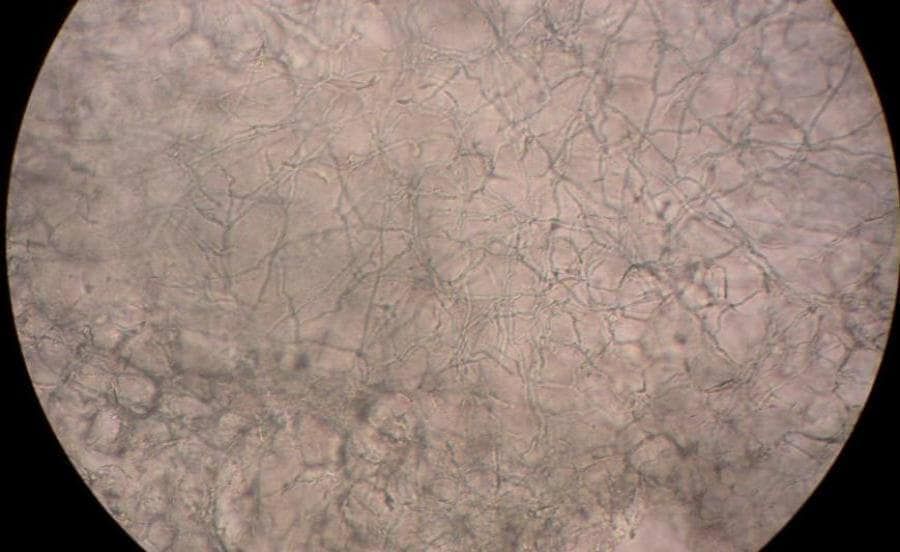

Blaasjeseczeem / Acrovesiculeus eczeem

Blaasjeseczeem is een bijzondere vorm van eczeem dat voornamelijk aan de handen en/of voeten voorkomt. De blaasjes of blaren blijven aan de handpalm en voetzool langer intact omdat hier de huid dikker is. De medische term is “acro-vesiculeus eczeem” ( acra = handen en voeten , vesikels = blaasjes). Een andere benaming is “dishydrotisch eczeem”. Deze benaming wordt niet meer gebruikt omdat men vroeger onterecht dacht dat het eczeem werd veroorzaakt door een stoornis van de zweetklieren. Blaasjeseczeem is één van de minst voorkomende vormen van hand -en voeteczeem. Er bestaan zowel acute als chronische vormen. Het blaasjeseczeem komt voornamelijk voor bij mensen onder de 40 jaar.

De oorzaak voor het ontstaan van blaasjeseczeem is in de meeste gevallen onbekend. Een uitzondering is de zogenaamde “ide” of overgevoeligheidsreactie. Een dubbelzijdig blaasjeseczeem aan de handpalmen ontstaat hierbij als reactie op een schimmelinfectie elders in de huid (bijv. een eenzijdige voet schimmel). Wel zijn er factoren bekend die blaasjeseczeem uitlokken of verergeren. Deze factoren zijn echter niet bij alle patiënten met blaasjeseczeem aanwezig of aantoonbaar.